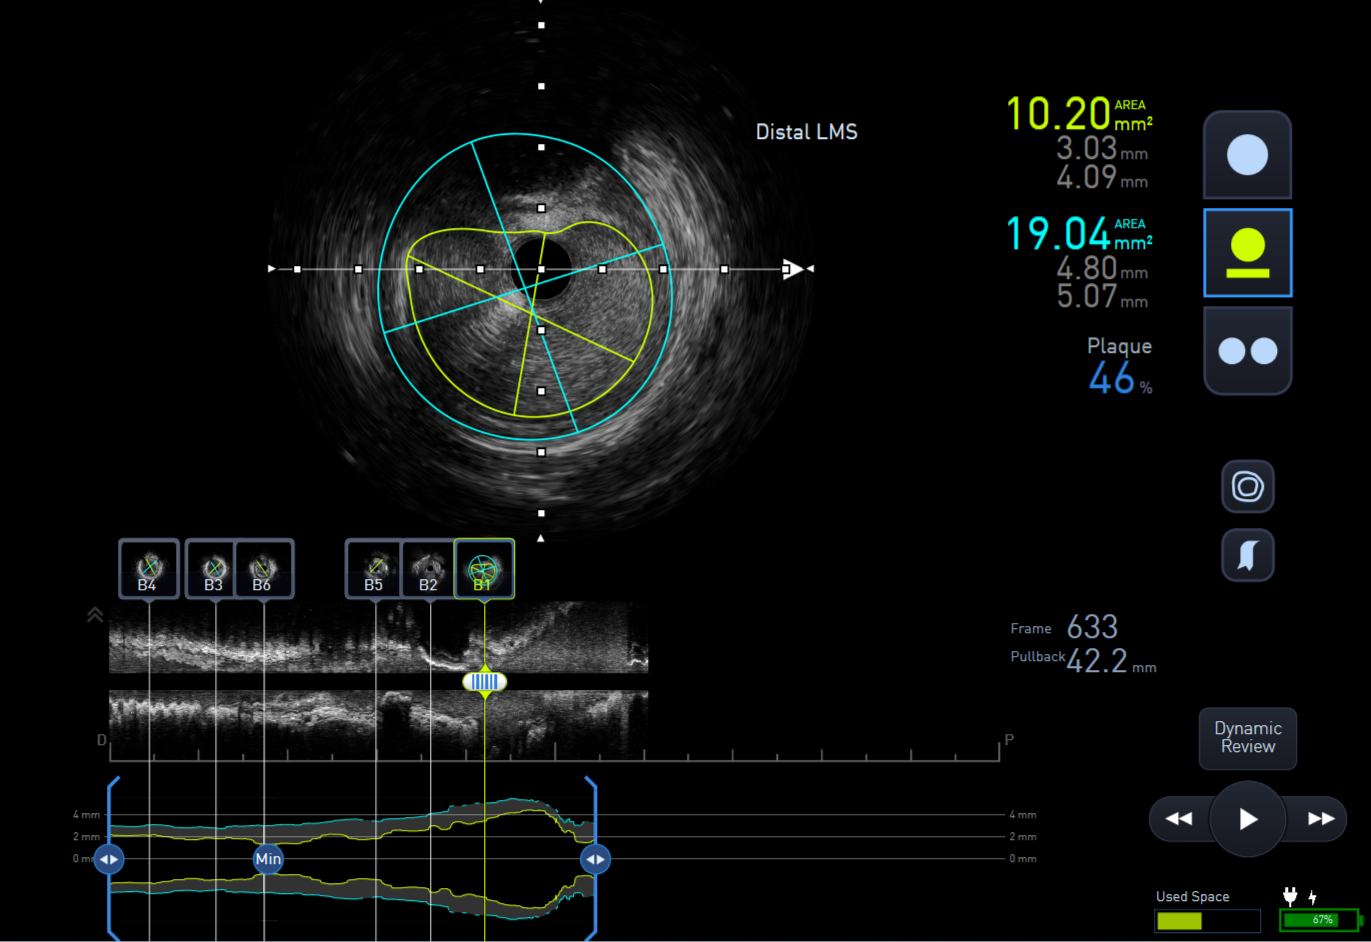

The lesion was predilated with a 2.0x15mm semi-compliant balloon to facilitate IVUS passing through the lesion. IVUS assessment showed distal Left main stem minimal lumen area (MLA) of 10mm2, proximal LAD 3.5mm2 and mid LAD 2.75mm2.